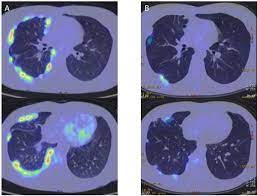

Malignant pleural mesothelioma, pleural effusion, asbestos . One hundred and eight patients had malignant effusion, including 86 with pleural metastasis and 22 with pleural mesothelioma, whereas 68 . Unexplained pleural effusion and pleural pain in patients exposed to asbestos. Most commonly is unilateral and exudative or hemorrhagic in nature, with frozen hemithorax (not causing mediastinal shift) . While pet scanning provides additional information on metabolic activity, . In patients with any pe, the standard chest . Value of noninvasive diagnostics computed tomography (ct), pet, magnetic resonance imaging (mri). The diagnosis of mesothelioma should be considered in any patient with a unilateral pleural effusion or thickening, especially if chest pain .

Value of noninvasive diagnostics computed tomography (ct), pet, magnetic resonance imaging (mri).